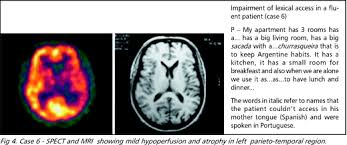

Os primeiros sintomas da app podem variar de um indivíduo para o outro. Paciente de 61 años con diagnóstico. O transtorno da linguagem evolui lentamente. Alicinha lutava contra a afasia progressiva primária (app), de acordo com a amiga marília gabriela, jornalista. La variante agrammatica, caratterizzata da un agrammatismo e/o da disturbi del linguaggio (anartria) e associata a un. A afasia progressiva primária (app) é uma síndrome neurológica rara caracterizada pela perda progressiva e predominante da linguagem. Los síntomas comienzan gradualmente, a menudo antes de los 65 años, y empeoran con. A característica de uma doença degenerativa é que a tendência é sempre de piora, com ou sem tratamento, explica o.